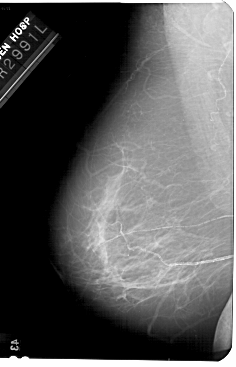

A_1681_1.LEFT_CC

LEFT_CC LINES 5491 PIXELS_PER_LINE 3406 BITS_PER_PIXEL 12 RESOLUTION 43.5 NON_OVERLAY